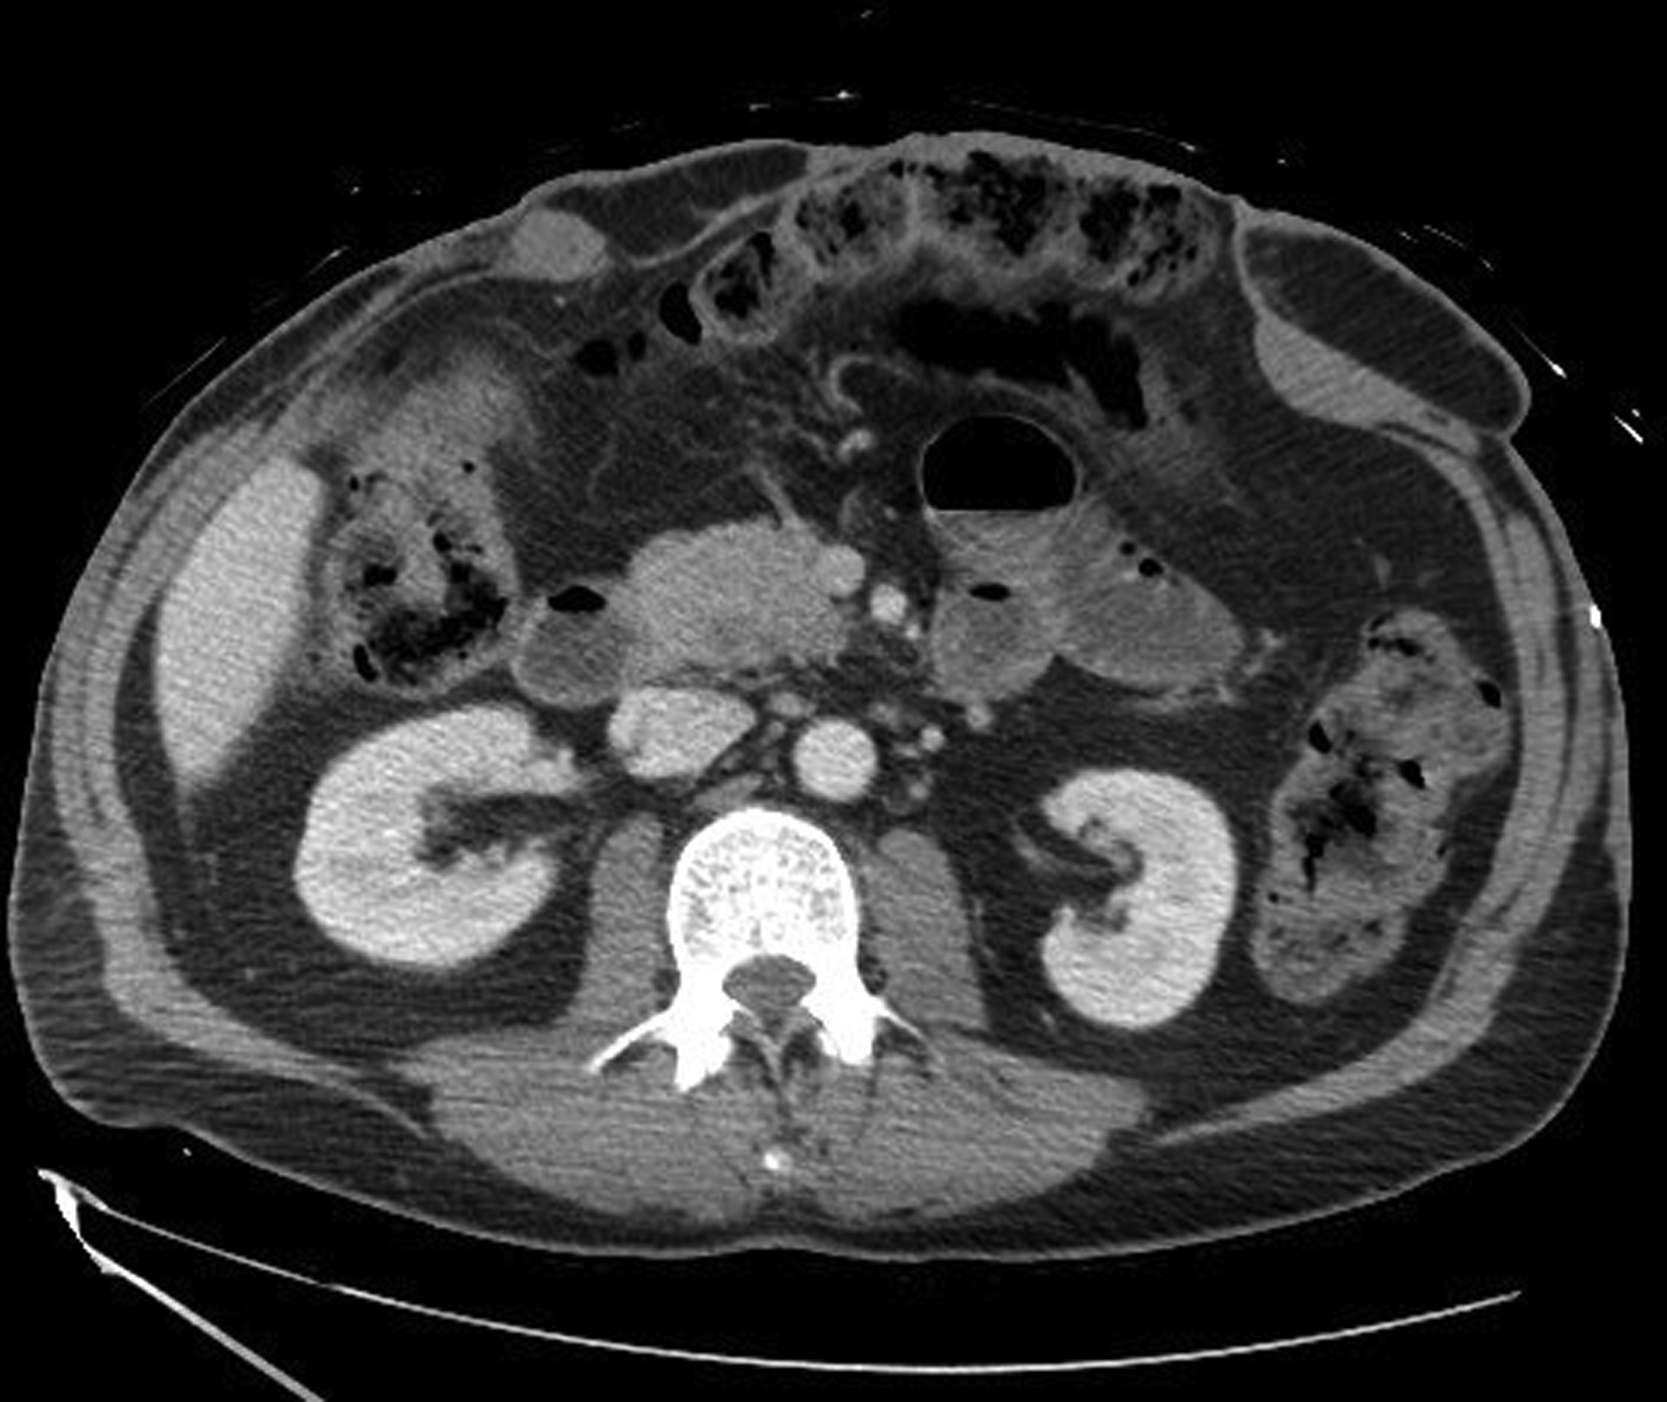

Under general anesthesia with the patient in the supine position, the plastic surgery portion of the procedure started after the herniated bowels were taken back to the peritoneal cavity and the peritoneal closure was achieved with additional component separation technique and placement of Prolene mesh by the general surgery service. The upper abdominal soft tissue defect measured 15 × 7 cm with significant undermining and deep space ( Fig. 26.2 ).